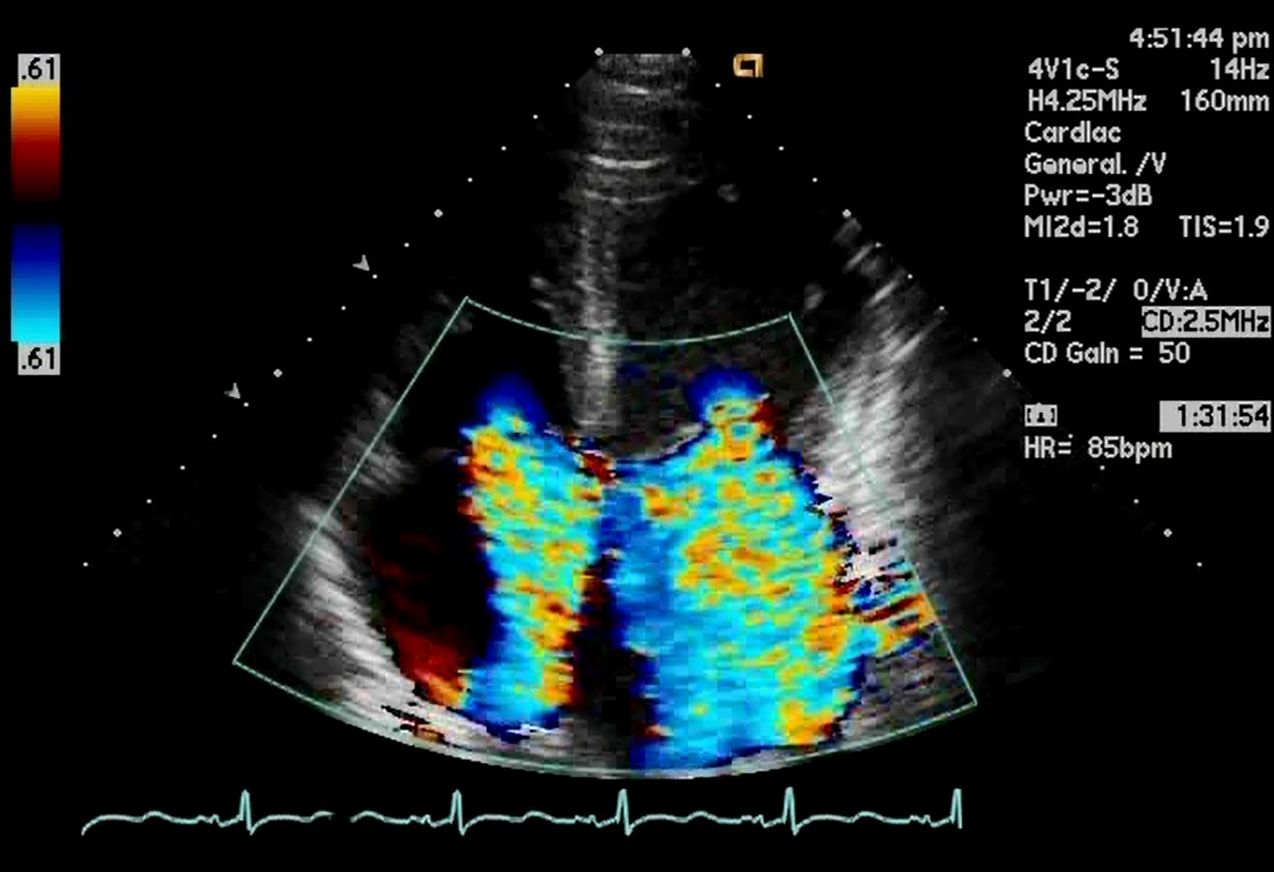

僧帽弁閉鎖不全症、三尖弁閉鎖不全症